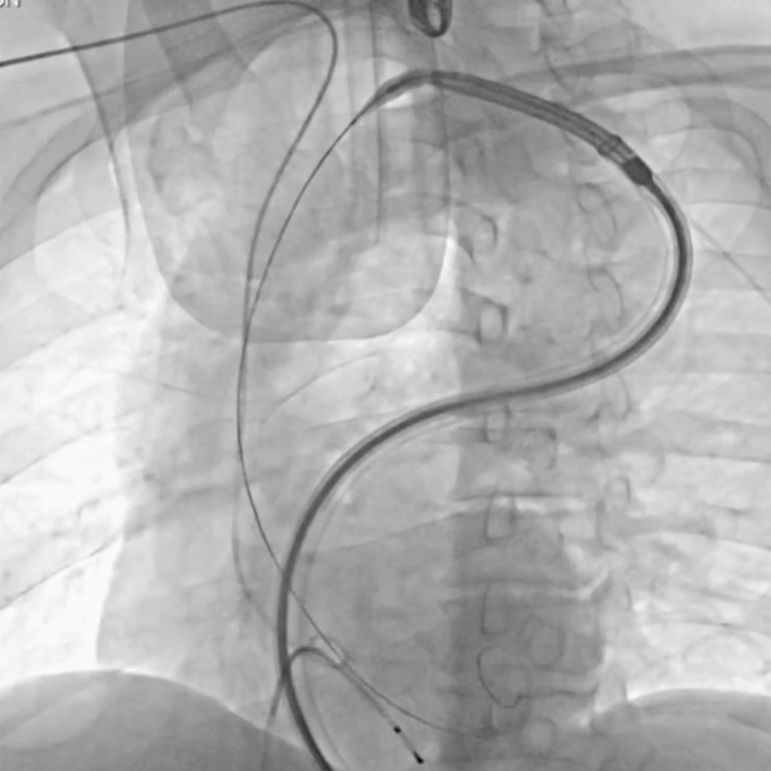

手术直播3:超大左房合并二尖瓣狭窄

本例患者存在严重心衰症状。心脏超声提示其左心房内径显著增大至176mm,属“超大左房”,并伴有重度二尖瓣狭窄,病情极为复杂危重。巨大的左房不仅显著增加了经房间隔穿刺及导管操作的技术难度与风险,也对术者建立稳定轨道、精准输送瓣膜的能力提出了极限挑战。

建立股静脉-房间隔-左房-左室-主动脉轨道

行二尖瓣球囊扩张

成功植入TAVR瓣膜